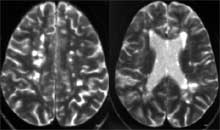

Первинно-прогресуючий РС мав місце у 67 (9,8%) хворих. Він виявлявся відносно рідко і пізно діагностували. Клінічні прояви ППРС характеризувалися одиничними моносимптомами на початку захворювання з подальшим прогредієнтним перебігом, розвитком грубих пірамідних, мозочкових симптомів, зниженням інтелекту у хворих. Діагностика ППРС на ранніх стадіях захворювання була дуже ускладнена, найчастіше проводилось вилучення запальних, дегенеративних захворювань головного і спинного мозку. На МР-томограмах виявлялися поодинокі великі вогнища демієлінізації з вираженим атрофічним процесом в головному мозку: розширенням шлуночкової системи, борозен, витончення звивин (Рис. 3а, б). Дослідження МТА сироватки крові та спинномозковій рідині в динаміці дозволило об'єктивізувати активність демієлінізуючого процесу. При цьому мало місце помірне підвищення МТА сироватки крові, яке коливалося протягом 1-2 і більше років у межах від 19,2 ± 0,72 до 26,4 ± 0,86 ум.од., а СМЖ - від 23,9 ± 1,2 до 29,8 ± 1,4 ум.од., що свідчило про повільне прогредиентном перебігу процесу.

Мал. 3а, б. Великий атрофічний процес з великими вогнищами демієлінізації при ППРС, (а, зліва) - півкулі, (б, справа) - стовбур головного мозку.